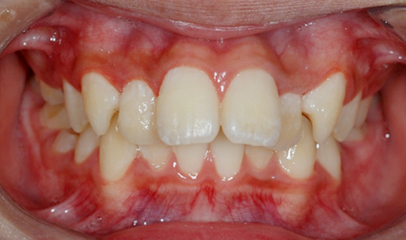

발치 돌출입 교정

전후 사례

발치 교정, 치료기간 약 2년

Before

After